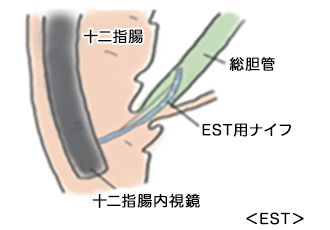

肝臓/膵臓領域の内視鏡治療

肝臓がん、胆膵がんはCTやMRI等の画像検査で診断し、 必要に応じて超音波内視鏡検査での精密検査も行います。

- 胆膵がんや胆管結石による胆道閉塞には、内視鏡的減黄術・ドレナージ術を行います。